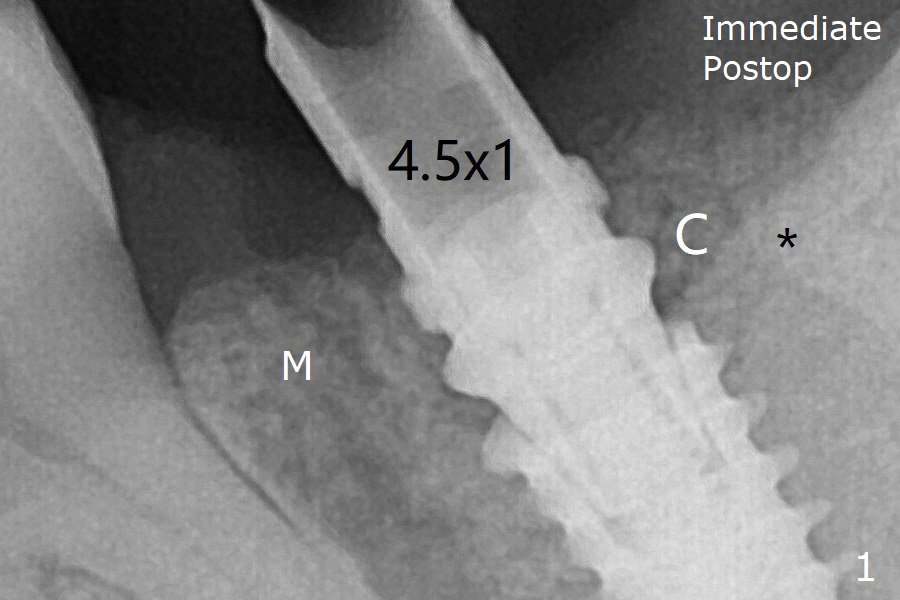

In fact the mesial crest is resorbed 3.5 months postop (Fig.9 M, as compared to that of preop and immediate postop in Fig.0,1). Continuous resorption may be associated with food impaction when a permanent crown is delivered. The preventive remedy would be socket shield, mesial and distal (Fig.0' M, D).